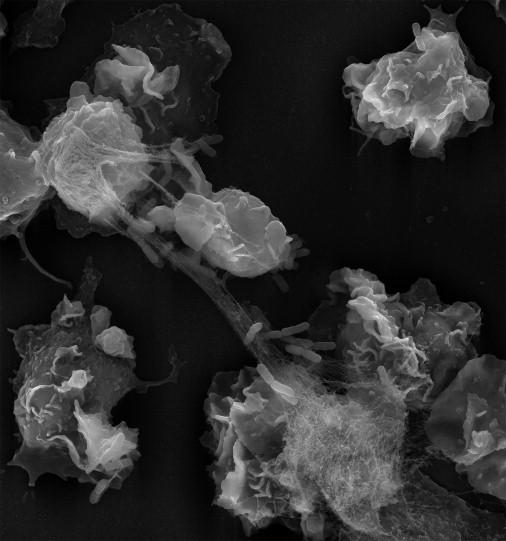

In your bloodstream, there are immune cells called neutrophils that, when faced with a pathogenic threat, will expel their DNA like a net to contain it. These DNA snares are called neutrophil extracellular traps or NETs. Researchers from Germany and the United States describe an important step in how these NETs are released and how they stop a fungus from establishing an infection in mice and human cells in the journal Developmental Cell .

Once a neutrophil is induced to release its NETs, it anchors itself in the tissue and breaks down its nuclear envelope: the barrier between the nuclear DNA and the rest of the cell. The researchers were intrigued by this, because normally cells only break down their nuclear envelope before they divide. Zychlinsky, Amulic, and colleagues hypothesized that neutrophils were using the same cell cycle proteins used for cell division to release the NETs.

To test this, the researchers inhibited the cell cycle proteins in mouse neutrophils, and found that indeed, fewer NETs were released. Consequently, mice that were no longer to efficiently release NETs were less able to clear fungal infections. Then, they observed human brains with fungal infections and confirmed that our neutrophils are also using cell cycle proteins.